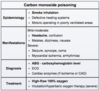

What is the likely diagnosis in a group of individuals that present with headache, nausea/vomiting, and confusion after eating at an indoor barbecue? Physical examination of one patient reveals tachycardia, tachypnea, and pinkish-skin hue.

Carbon monoxide poisoning

diagnosis is confirmed by measuring carboxyhemoglobin levels (> 3% in non-smokers; > 10% in smokers)